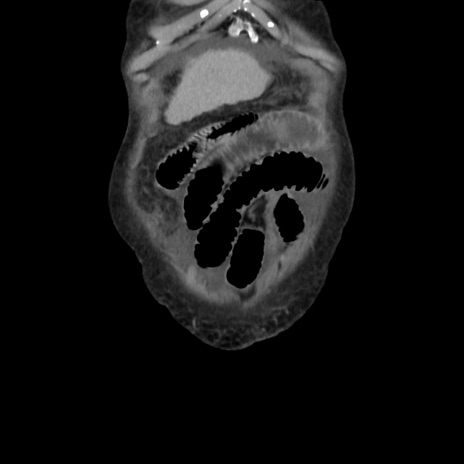

矢状断像